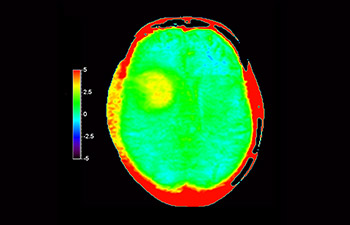

Brain with glioblastoma

with 3D APT